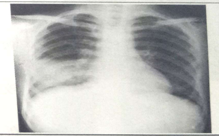

影像診斷樣題(答題要點(diǎn))試題1:男性,26歲,受涼后寒顫高熱,咳嗽,咳鐵銹色痰5天(2分)

A.肺癌

B.氣胸

C.正常胸片

D.肺炎

E.胸腔積液

答案:D